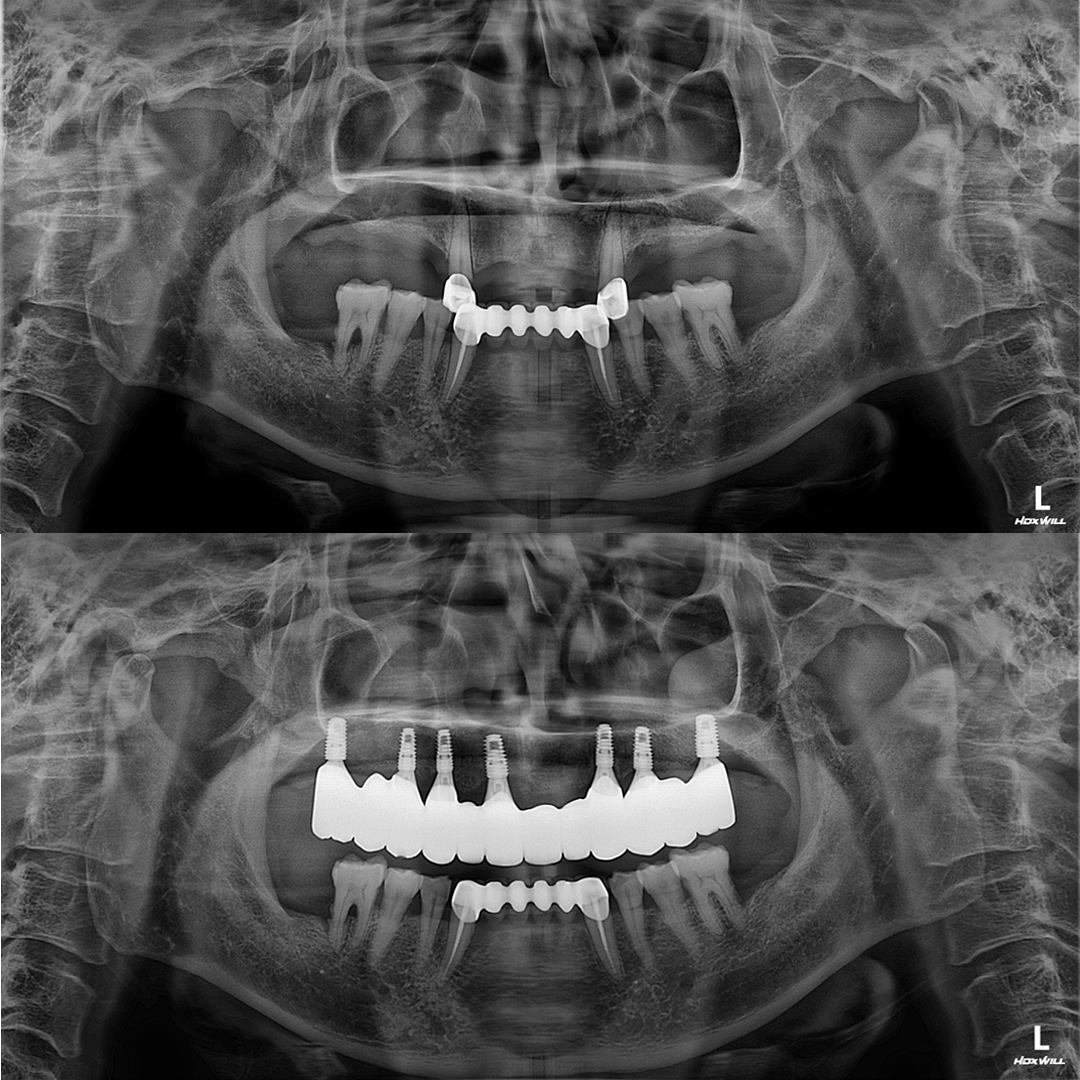

디지털 기술로 더 정확하고 확실하게

디지털(스마트) 임플란트

디지털 스캐닝 기술을 이용해 정교한 3D 모델을 만들고

임플란트의 정확한 위치에 식립하여 높은 정밀도와 맞춤형 치료를 제공합니다.

평균 악당 30분의 빠른 식립시간, 치료 케이스 다수 보유

전체 임플란트

상·하악 전체 치아를 대체하는 임플란트로 최소한의 식립을 통해

자연치아와 비슷한 기능을 수행할 수 있도록 합니다.